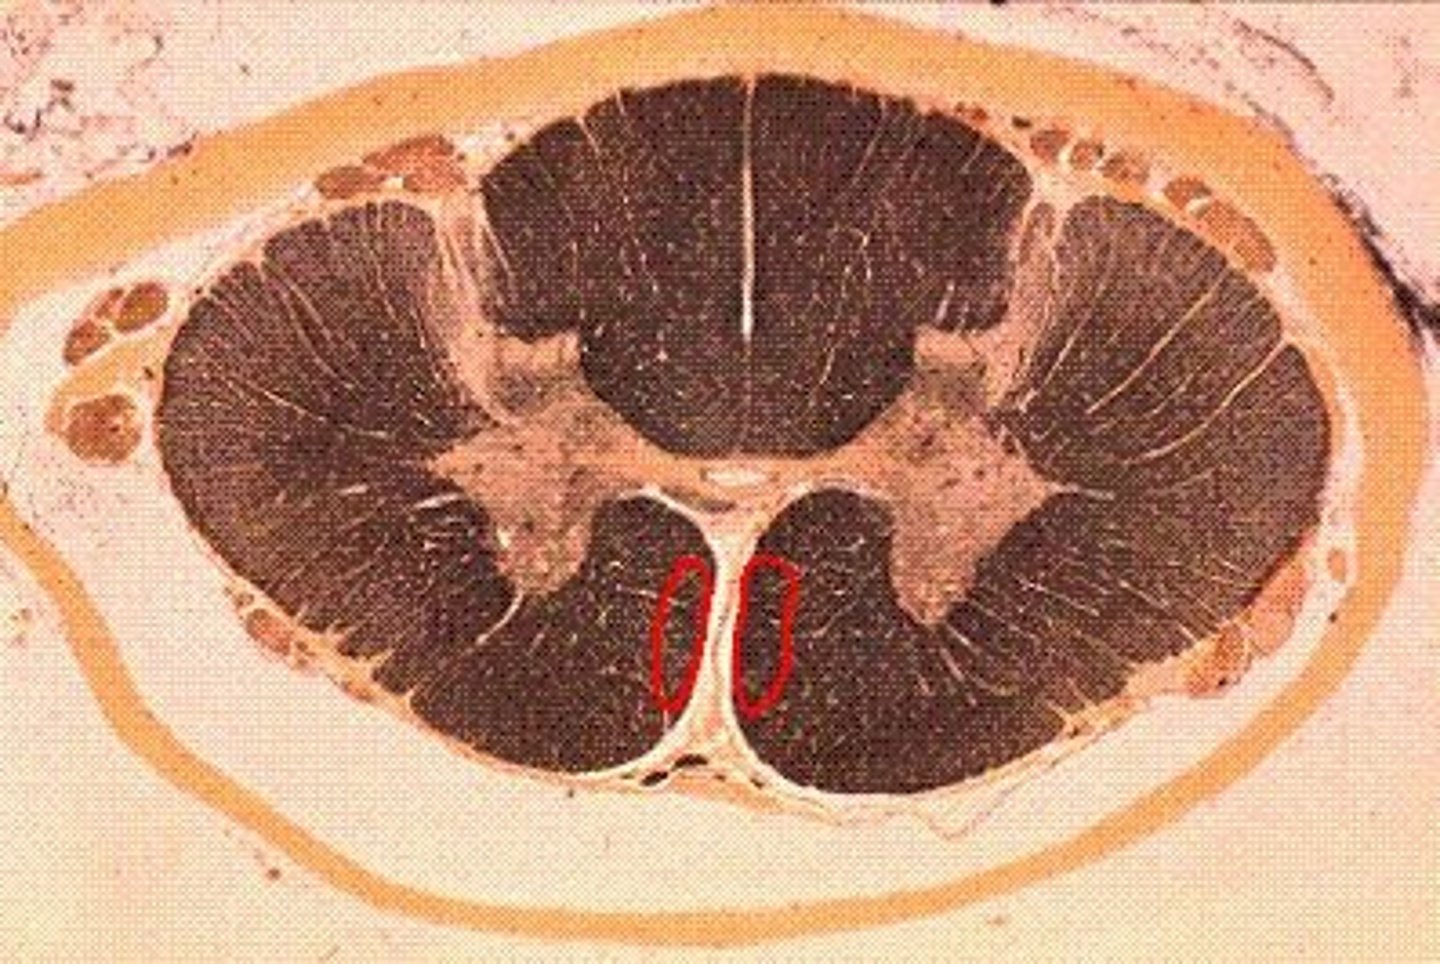

Inferior Cerebellar Peduncles

Connect medulla oblongata to cerebellum

Contains an ipsilateral tract that receives input from the spinal cord - dorsal spinocerebellar

Contains both ipsilateral and contralateral tracts connecting to the reticular and vestibular systems - vestibulospinal and reticulospinal

Contains a contralateral tract connecting to the inferior olivary nucleus - olivocerebellar